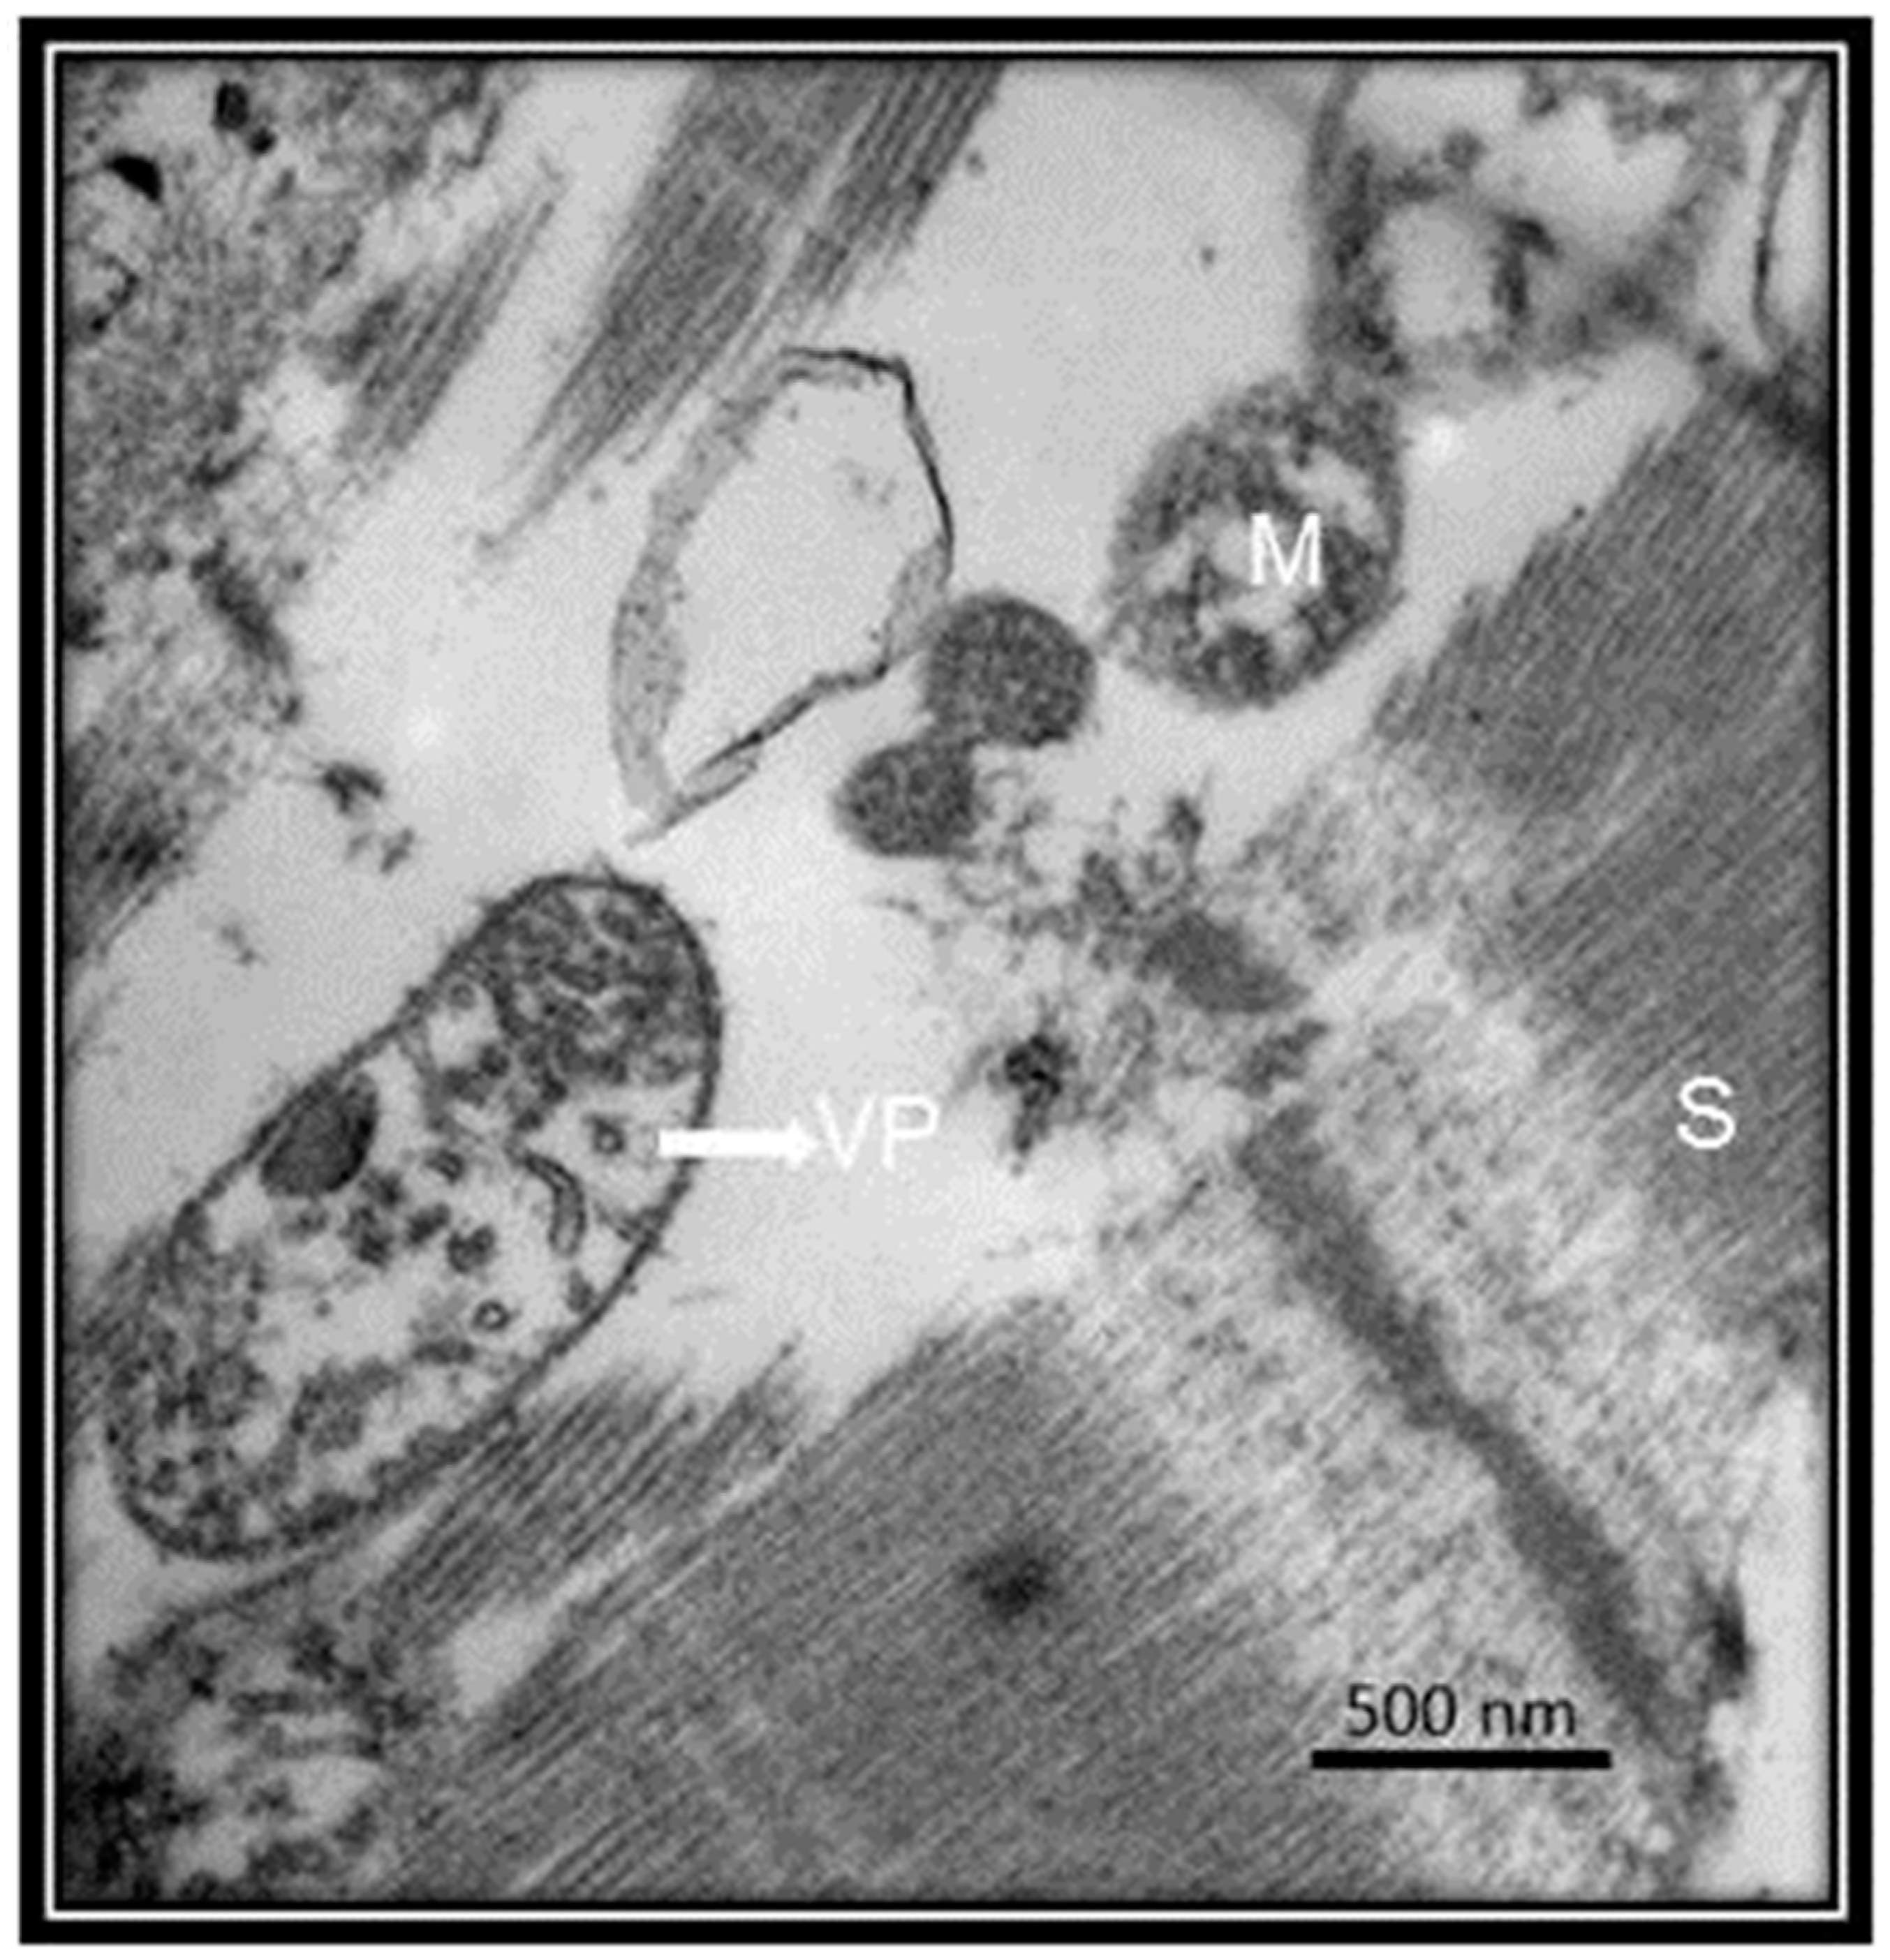

- Qu, C.; Zhang, S.; Li, Y.; Wang, Y.; Peppelenbosch, M.P.; Pan, Q. Mitochondria in the biology, pathogenesis and treatment of hepatitis virus infections. Rev. Med. Virol. 2019, 29, 2075. [Google Scholar] [CrossRef]